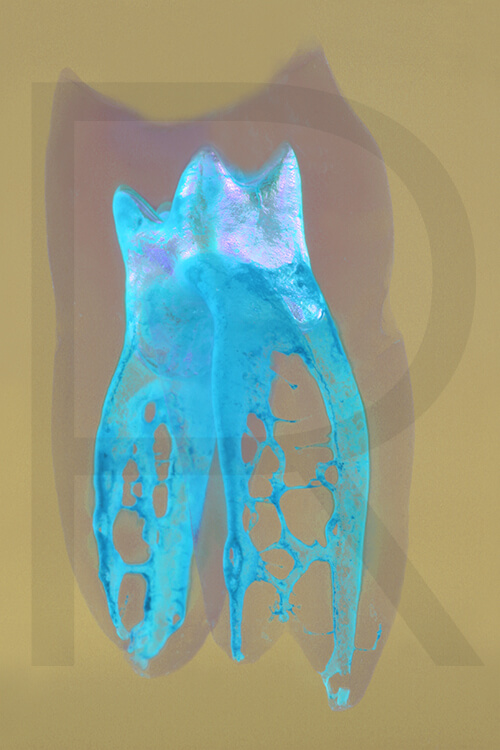

Bildauswahl mit schwebender Aufhängung

Sie haben hier die Möglichkeit, besondere Arbeiten

(© Dr. Holm Reuver) für Ihre Praxis zu erwerben.

Bitte wählen Sie aus klassischen Varianten, Pop Art, Collagen oder Mehrfach-Varianten.

- Foto hinter 3mm Acrylglas, rahmenlos

- hochwertige, unsichtbare Aufhängung, "schwebend“

- Hoher UV-Schutz für lang anhaltend strahlende Farben

- Bruchsicher und leichter als Glas

- Beeindruckende Farben und brilliante Tiefenwirkung

- Druck erfolgt ohne Wasserzeichen

- Bildgröße: 90 x 60 cm, Hochformat

Preis: 490,00 Eurozuzüglich 16,90 Euro Versand & Porto innerhalb Deutschlands, weiterer Versand auf Anfrage

Wenn Sie Interesse an den Fotos transparenter Zahnpräparate haben, bieten wir hier die Möglichkeit einige Versionen als Acrylbilder (alle Detailinformationen zu Größe und Preis siehe obige Auswahl) zu bestellen.

Die Bilder sind nicht nur zur Praxisverschönerung geeignet sondern auch eine wertvolle Unterstützung bei der Patientenberatung vor endodontischen Behandlungen.